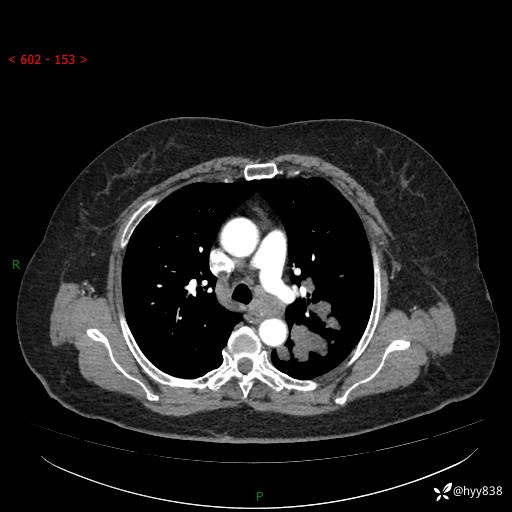

老年女性,左上肺结节8年。典型又不典型,看你如何解读---结果公布(值得分析)

主诉:检查发现左上肺结节8年,较前增大。

简要病史:患者于8年前体检行胸部CT检查发现左上肺结节(4mm),患者平素间断咳嗽咳痰,无心慌、胸闷、胸痛、呼吸困难、低热、盗汗,无头痛、头晕,无腹痛、腹胀等不适,未行特殊处理,定期复查。2023-09-21胸部CT示左上肺结节(2cm)较前增大,2024-02-01胸部CT示左上肺尖后段(39*32mm),左侧肺门及纵隔淋巴结增大,现患者欲求手术治疗,遂来我院就诊,以“左上肺结节”收入我科。 患者自起病以来,精神可,睡眠可,饮食可,大小便正常,体重无明显改变。

辅助检查:CT

胸部CT平扫

增强(动脉期+静脉期)